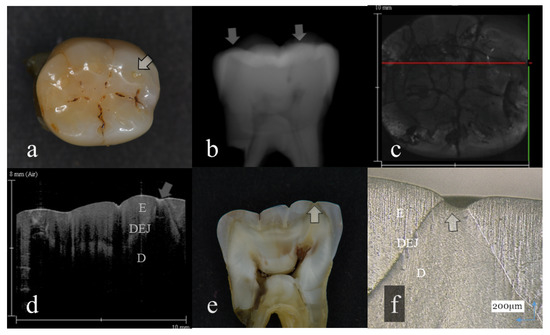

Figure 1.

Slight enamel wear (score 1): (a): Occlusal view. Visibly, evidence of occlusal tooth wear was not observed; (b): Digital intraoral radiography; (c): Optical coherence tomography (OCT) en face intensity projection; (d): Swept-source (SS)-OCT image. Occlusal enamel and underlining dentin were distinguished by the dentin enamel junction (DEJ) (arrow); (e): Histological view; (f): Confocal laser scanning microscopy (CLSM) image of histological view. A tip of the cusp was slightly cracked (arrow). However, the anatomical shape of the cusp was maintained. The corresponding dynamic slicing 3D video is in Supplementary Materials: Video S1. The upper right is a cross-sectional image. Lower right is an en face image.